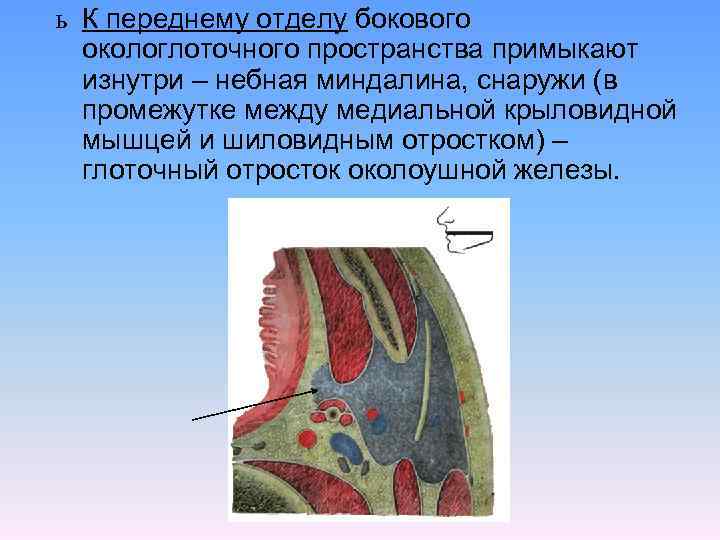

Анатомия межплеврального пространства